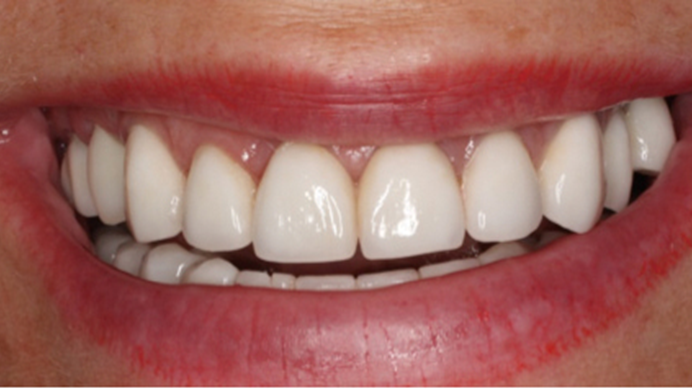

Clinical case: Extraction, immediate implant placement, & provisionalization

- Courtesy of Dr. Iulian Filipov, Romania -

Keywords

AnyRidge, R2GATE, guided surgery, immediate placement, immediate provisionalization, initial stability, Dr. Iulian Filipov, #25, maxillary posterior, immediate loading, Mega ISQ

“Patient’s smile was recovered on the day of surgery

with reliable & highly-aesthetic results using AnyRidge & R2GATE. ”